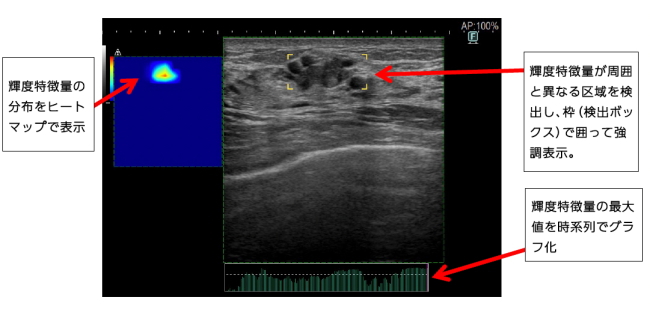

富士フイルムホールディングス(富士フイルムHD)<4901>(東証プライム)は10月24日、6900円(119円高)で始まった後も上値を追い、出直りを強めている。20日付で2本のリリース(乳腺クリニックや検診バス向けのコンパクト型デジタルマンモグラフィの11月1日発売開始、乳房超音波検査の支援機能「eScreening(イースクリーニング)」提供開始)を発表しているほか、NY市場で前週末21日に上げたこと、24日には中国の複合機工場の閉鎖が伝えられたこと、などが買い材料視されている。

乳腺検診のリリースによると、乳がんは、日本のがん統計によると、日本人女性の中で最も罹患者数が多いがんになる。超音波による乳房検査(乳房超音波検査)は、日本人に多いとされる乳腺組織の割合が高い「高濃度乳房(デンスブレスト)」でもがんを検出しやすい特長があるため、マンモグラフィ検査との併用で早期乳がんの発見率がさらに高まることが知られているという。(HC)(情報提供:日本インタビュ新聞社・株式投資情報編集部)